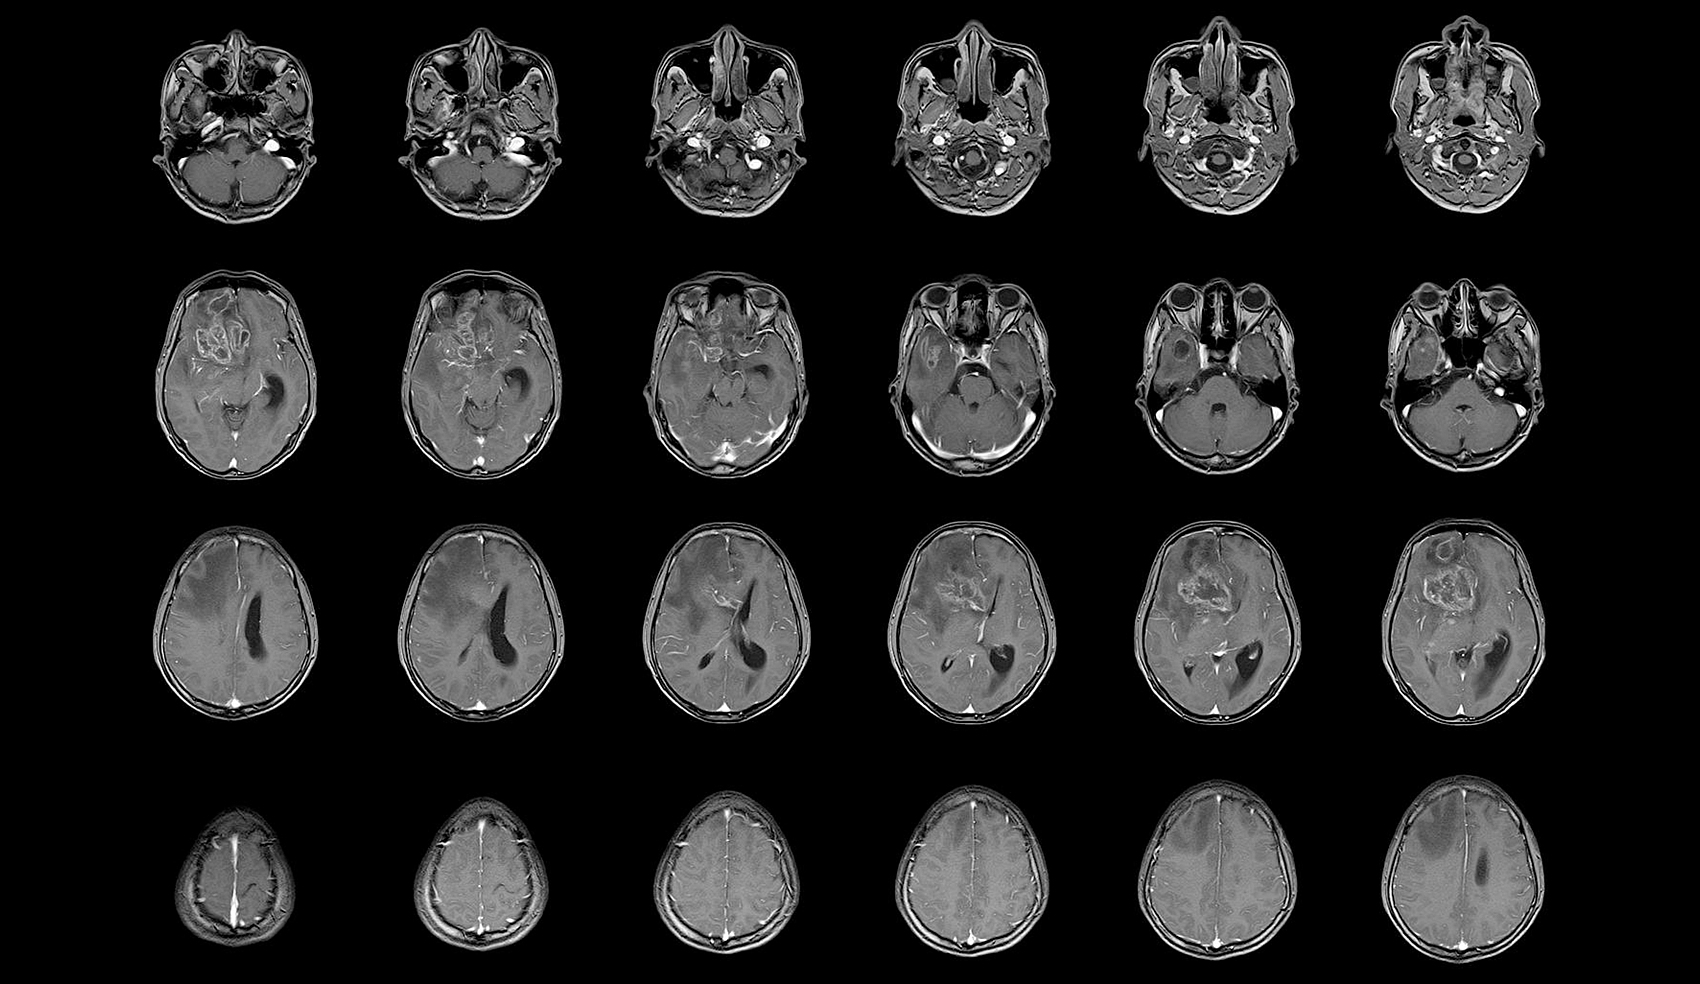

昆明腦膜瘤放射治療方式有哪些

達州腦膜瘤放射治療方式,達州腦膜瘤醫院哪家好-達州醫科腫瘤醫院腦膜瘤(Meningiomas)是起源于腦膜及腦膜間隙的衍...

放射治療是一種腦膜瘤常用的治療方法

腦膜瘤放射治療醫院,達州腦膜瘤醫院哪家好-達州醫科腫瘤醫院腦膜瘤是一種發生在腦膜(腦部外層覆蓋的薄膜)上的腫瘤。它通常是...

放射治療如何對腦膜瘤進行治療好不好

腦膜瘤放射治療技術,達州腦膜瘤醫院哪家好-達州醫科腫瘤醫院腦膜瘤是一種起源于腦膜的腫瘤,它可能會對患者的生命和健康造成重...

放射治療對腦膜瘤的治療效果是非常顯著的

腦膜瘤放射治療效果,達州腦膜瘤醫院哪家好-達州醫科腫瘤醫院腦膜瘤是一種比較常見的顱內腫瘤,通常生長緩慢,但如果不及時治療...